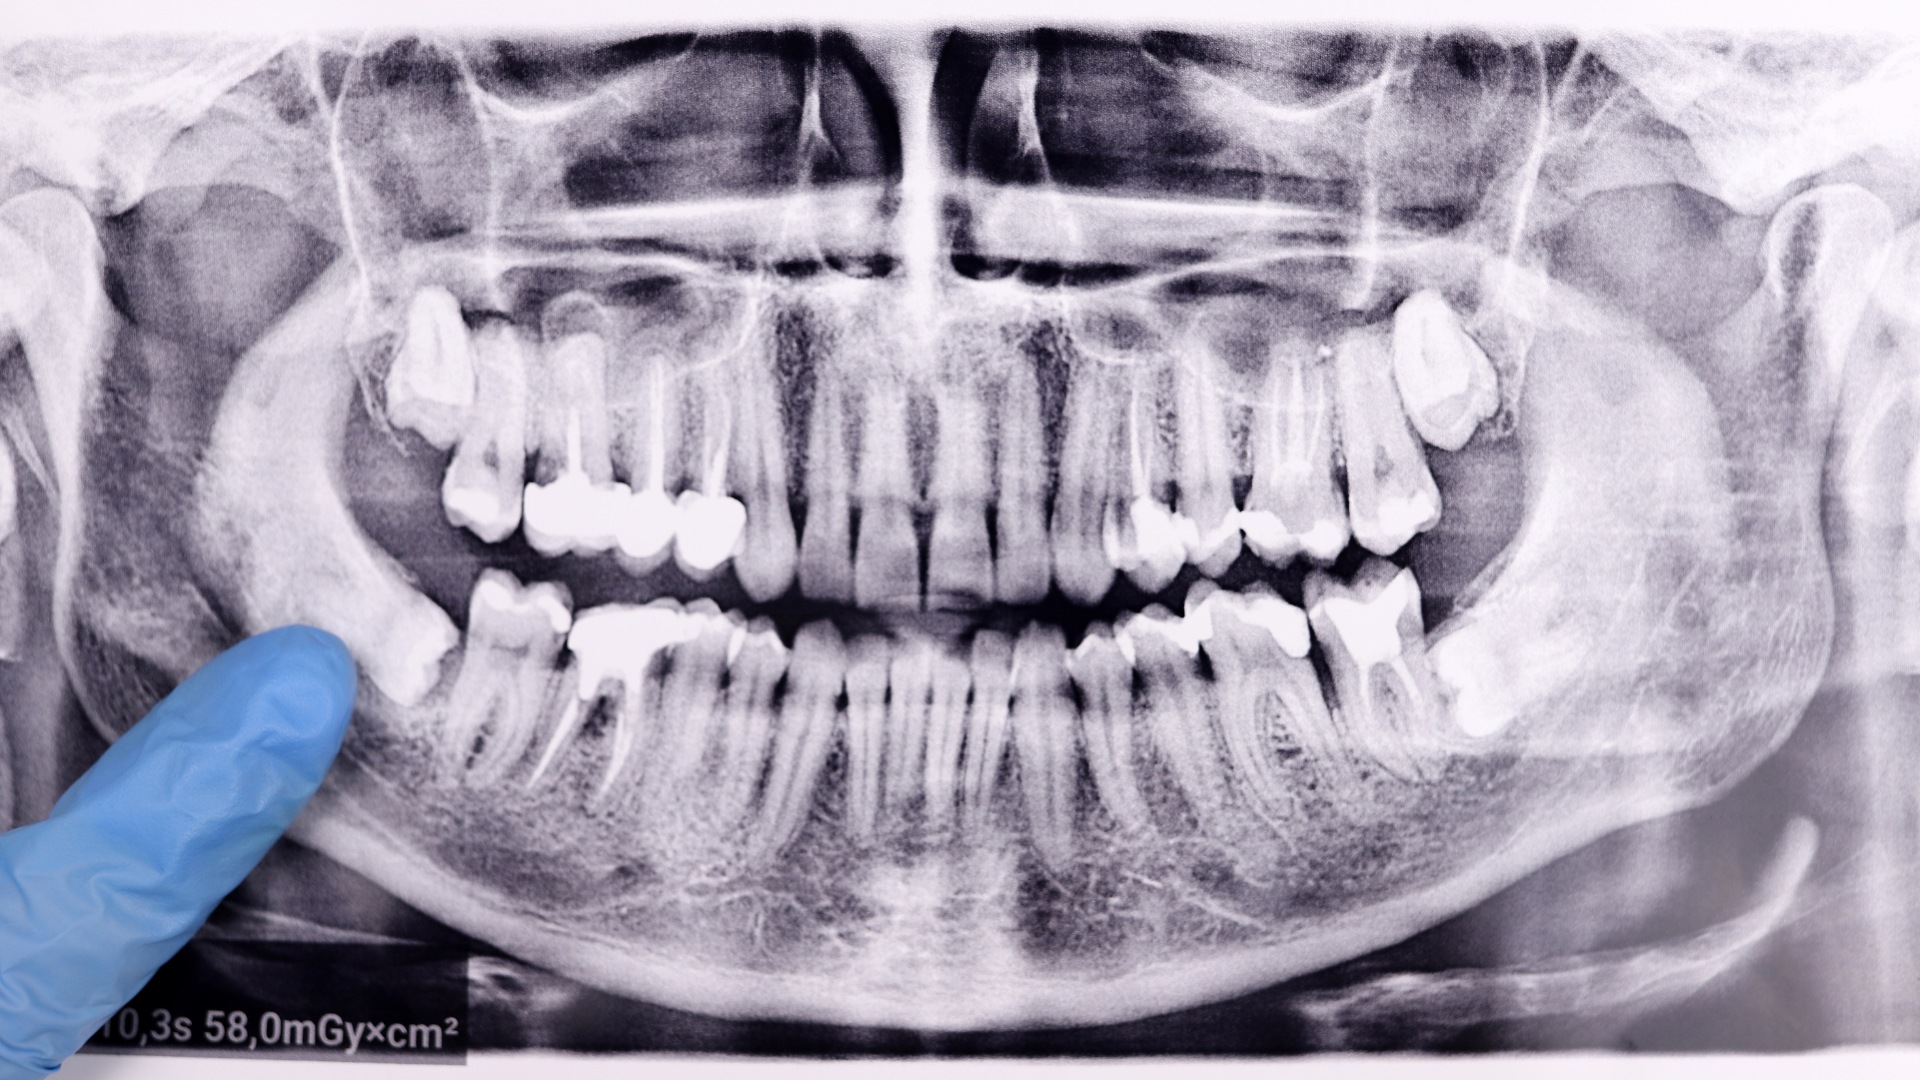

A professional evaluation is essential for determining whether wisdom tooth removal is necessary. Dental imaging and clinical exams provide valuable insight into tooth position and potential risks. This information helps guide decision-making. Accurate assessment is critical.

Moreover, working with a dental provider ensures that all factors are considered before proceeding. This reduces uncertainty and helps patients feel more confident in their decision. Professional guidance supports better outcomes.